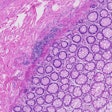

The study demonstrated how researchers can take whole-slide images (WSIs) produced from routine hematoxylin and eosin (H&E)-stained NSCLC tumor tissue slides and use them to train an AI model to potentially perform histologic review by pathologists.

Furthermore, based on the regions of interest (ROI) that most strongly contributed to the deep-learning (DL) algorithm’s ability to predict progression versus no progression, it appeared that the AI's basis of prediction relied not only on subtle and complex histologic features of tumor cells but also non-tumor cells and the tumor microenvironment, according to the study's authors.

As a potential AI assistant for pathologists, this DL model started with data and biopsy images of diagnostic WSIs of 158 patients with stages I to III NSCLC (65 metastases positive [Met+], 93 metastases negative [Met-] within five years). All cases were assessed for tumor adequacy. From each scan, regions of high tumor cellularity and surrounding tumor microenvironment were annotated by one reviewing pathologist.

Importantly, the DL model identified features that were not readily discernable by a trained pathologist (such as tumor grade, necrosis, lymphocytic infiltration, spread to airway spaces), and it even outperformed careful histologic review by four expert pathologists, the authors wrote.